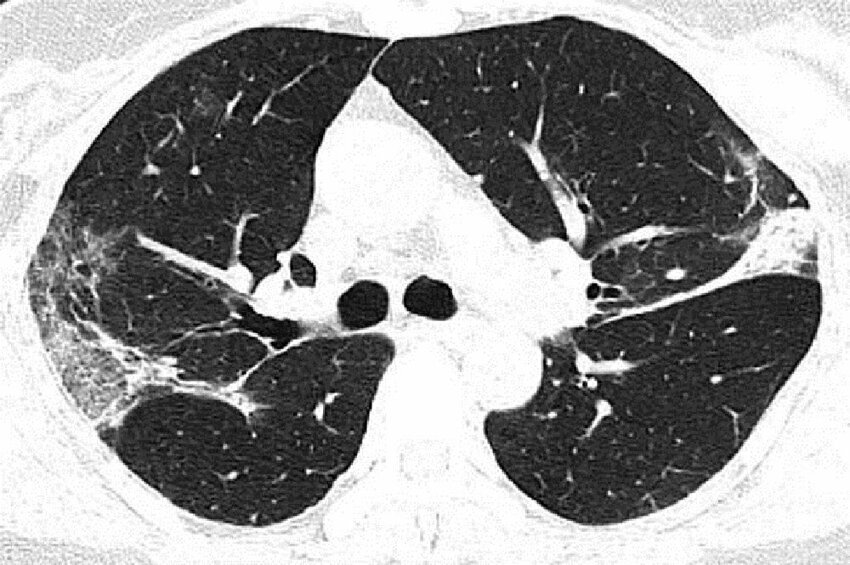

Снимок лёгких зараженного пациента

Опубликованы рентгеновские снимки и компьютерная томография 44-летнего китайского пациента. По ним хорошо видно, как именно вирус разрушает легочную ткань. По утверждениям медиков, повреждения похожи на те, что обнаруживались в легких жертв атипичной пневмонии и ближневосточного респираторного синдрома.

На фото видны все увеличивающиеся со временем белые пятна в нижней части дыхательных органов. Радиологи называют это симптомом "матового стекла", который отражает различные патологические изменения в легочной ткани.

Отмечается, что на фото заметно присутствие жидкости в легких мужчины, которое постепенно становится все более выраженным (проследить можно по изображению).